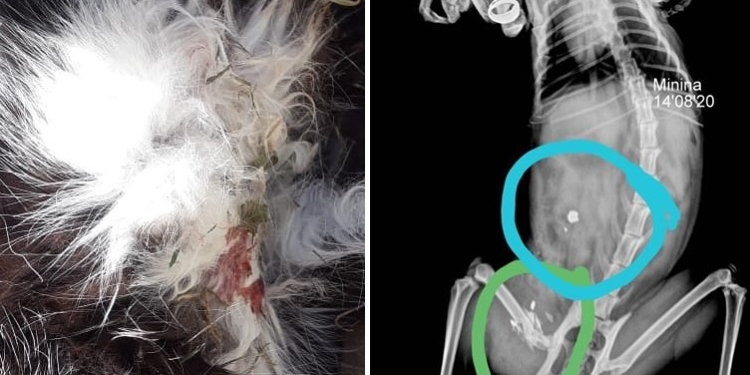

Mary, su dueña, contó a Info Más que advirtió que su gatita estaba herida el miércoles al mediodía, cuando regresó a su vivienda después del trabajo. La llevó al veterinario, le realizaron ecografías, fue medicada y el viernes en la placa, se descubrió que tenía un balín alojado y huesitos estallados en una pata.

Minina llegó a su hogar tras pocas semanas de vida y si bien parecía que podría sobrevivir al ataque, falleció a las 14 horas de este sábado convirtiéndose en otra víctima de un nuevo caso atroz de maltrato animal.